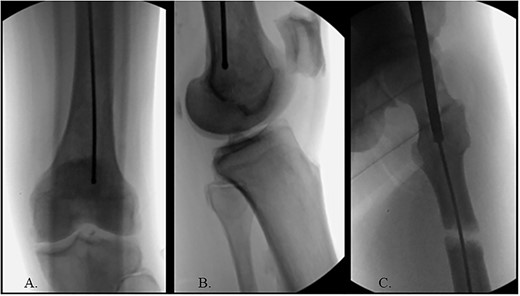

(A) Canulated cutter tool creating a new path in the proximal femur; (B) rigid canulated reduction rod directing the guidewire across a reduced fracture held with a proximal bone hook and distal ball spike pusher; (C) center positioned ball-tipped guidewire at the knee on the AP XR; (D) center positioned ball-tipped guidewire at the knee on the lateral XR.

The ball-tipped guidewire was extracted, and a sharp cannulated cutter created a novel path in the proximal segment (Fig. 4A). A rigid nonunion reamer (DePuy Synthes©, Raynham, MA) was advanced to widen the canal. Closed reduction was lost and so a lateral incision was made at the level of the fracture and a percutaneous reduction was achieved through use of a proximal bone hook and distal ball spike pusher (Fig. 4B).

The hip was extended, and a ball-tipped guidewire was successfully passed across the fracture site to a center–center positionwithin the canal at the level of the knee (Fig. 4C and D). Sequential 0.5-mm reaming from 9 to 13 mm prepared for an 11 × 400 mm, 125° Gamma3® intertrochanteric rod (Stryker© Kalamazoo, MI), with a 95-mm cephalomedullary screw and ×2 distal lateral to medial interlocking 5.0-mm screws (Fig. 5A–D). Through the course of the procedure, 400 cc of blood loss necessitated two units of packed red blood cells.